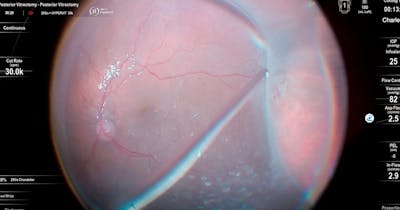

The RETINAWS panel led by Kourous Rezaei, MD, discuss techniques for vitreoretinal surgery and rare surgical cases.